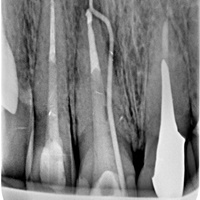

Wskazania do wykonania resekcji zębów 21, 22. Prawie niewidoczna blizna pooperacyjna.